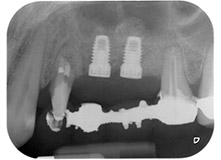

Имплантологичното ложе е подготвено в позиции 25 и 26 с ротиращи инструменти, използвайки обратен наконечник 20:1 с усъвършенстван и мощен имплантологичен мотор (Implantmed, W&H) (Фиг. 8).

Преди поставянето на имплант, и последвалото потвърждение за непокътната Шнайдерова мембрана (Фиг. 9), вътрешният синус е повдигнат и в двете места на имплантите с помощта на ксеногенен костозаместващ материал (Bio-Oss, Geistlich Biomaterials) (Фиг. 10).

Имплантите (Restore, Keystone Dental, диаметър 3,75 mm, дължина 8.0 mm) са поставени с имплантологичен мотор

(Фиг. 11 и 12).

Дефицитът на кост около имплантите, от мезиален аспект на зъб 27 и около букалния корен на зъб 24, е запълнен с ксеногенни костозаместващи частици и покрит с абсорбираща колагенова мембрана (Bio-Gide, Geistlich Biomaterials) за GBR аугментация (Фиг. 13 и 14).

Накрая, след периостален разрез, мястото е пасивно зашито с коронарно напреднало ламбо, използвайки 5-0 абсорбиращ конец (Фиг. 15). Следоперативната рентгенова снимка показва, че и двата импланта са в правилна вертикална позиция (Фиг. 16).